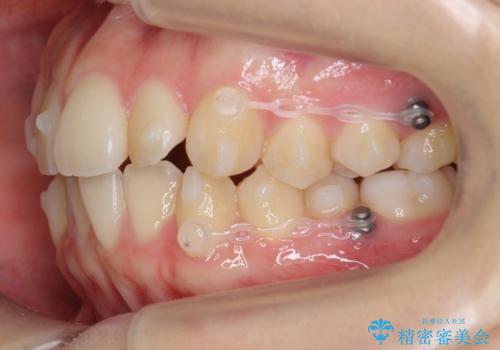

- 矯正装置

- インビザライン

スペースを確保するために、歯をわずかに削る処置、奥歯を後ろに下げる処置(インプラント矯正)を行っています。

- 104.5万円(マウスピース矯正 93.5万円、矯正用スクリュー11万円)費用は治療当時の料金となります